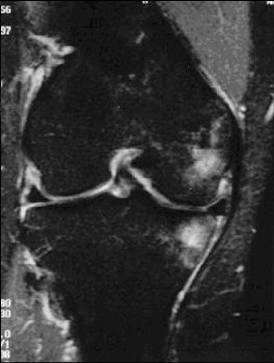

An 18-year-old man sustains a twisting injury to the left knee while playing football. An MRI scan is shown in Figure 48. What is the most likely diagnosis?

lateral mensicus tear

MRI scan shows a displaced, bucket-handle lateral meniscus tear. The sagittal view shows the typical “large anterior horn” sign, or “double meniscus” sign in which the displaced bucket-handle fragment appears just anterior to the native anterior horn of the lateral meniscus. The presence of the fibula on the sagittal view confirms this as the lateral compartment. The image is lateral and the cruciate ligaments are not visualized. The articular cartilage shown does not demonstrate an osteochondral lesion.